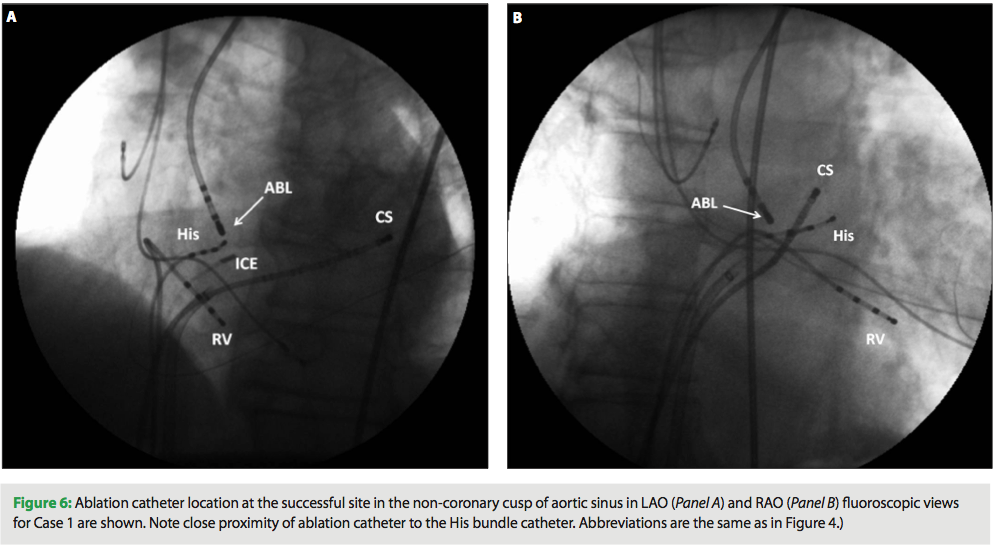

The ablation catheter was advanced to the aortic root under fluoroscopic and intracardiac echo guidance (Figure 4, Panels A and B). At this location, low amplitude, multicomponent atrial electrograms with activation times earlier than those in the His bundle region were noted (Figure 5, Panel A). Ablation at this location terminated SVT in 2.6 sec (Figure 5, Panel B). Ablation catheter location at the successful site in NCC is shown in Figure 6 (Panels A and B). Two 60-second applications were delivered at this location (30 W, 55° C), and AT was no longer inducible despite aggressive testing. Patient remained arrhythmia-free at one-month follow up. There were no complications.